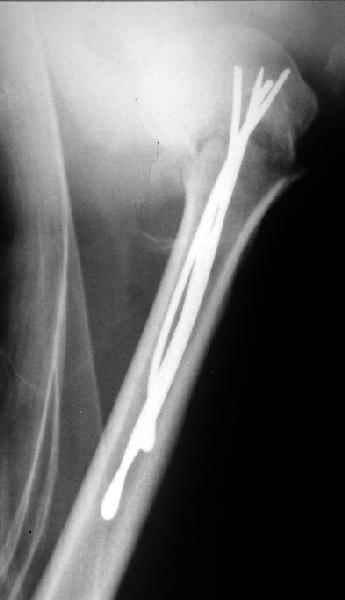

Женя, а как ты водишь спицы, в смысле, как делаешь входное отверстие, и как в него проводишь V-спицу? А то о дна из спиц, та, у которой не дошла до головки одна палочка буквы V, как-то выглядит на рентгенограмме, как будто или через очень большое отверстие введена, или каждая половинка через отдельные отверстия.

Мне кажется, проблема в том, что не все концы спиц зашли в головку, и зашедшие - недостаточно далеко прошли.

Спицы провожу по передней и задней поверхностям плечевой кости через 4,5 мм отверстия на разных уровнях.

Идеей презентации случая была демонстрация важности постоп Рг - хотя казалось бы все было сделано под флюороскопическим контролем и интраоперационно подозрений на нестабильность не возникло, а такая вот

неожиданность...

Уточни - обе части буквы V вводишь в одно отверстие? А то по снимкам выглядит, что в разные.

V-спица проводится через 4,5 мм отверстие. Видимо, из-за разной длины вторая половина спицы *пролетела* мимо отверстия, что и привело к вторичному смещению костных фрагментов.